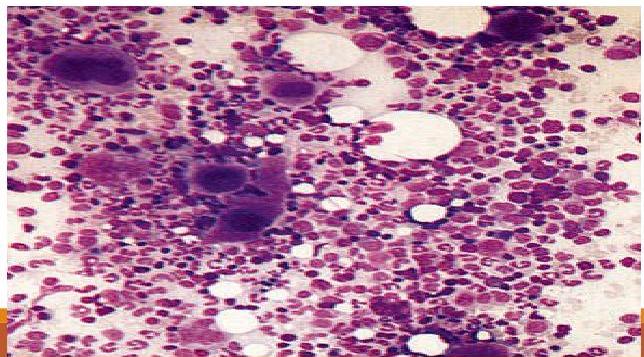

- Bone Marrow Aspiration: Shows normal granulocytic/erythrocytic series with normal or increased megakaryocytes. Indicated only for atypical features or therapy failure.